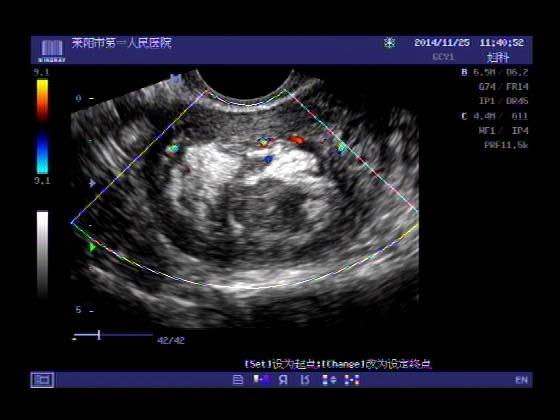

超声入门贴379---------粘膜下肌瘤(阴超的魅力)

女,43岁,月经量多3个多月,加重一个月

外院彩超检查提示:子宫后肌壁略高回声团------肌瘤?息肉?,盆腔少量积液

今天来我院检查:

巧妇难为无米之炊,经腹部超声确实很难定,阴超一目了然,乡镇医院诊断水平的提高更迫切的需要高档仪器的引进!